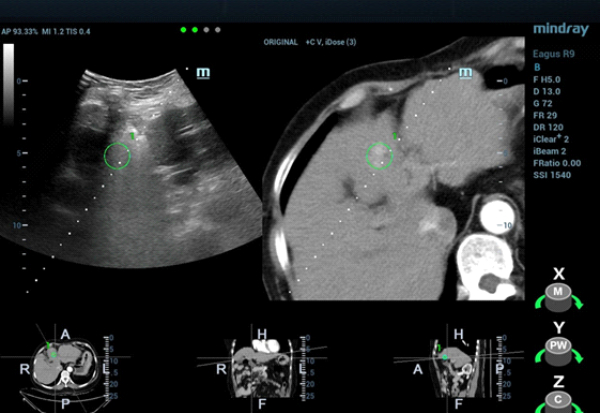

W konwencjonalnym obrazowaniu USG w skali szaro?ci nie uda?o si? uwidoczni? guza w segmencie IV zaobserwowanego w badaniu TK jamy brzusznej. W badaniu USG z kontrastem (contrast-enhanced ultrasound, CEUS) zmiana wykazywa?a wzmo?one unaczynienie w fazie t?tniczej (Obraz 2.) z izointensywnym wzmocnieniem w fazach wrotnej i pó?nej (Obraz 3.)./p>

U pacjentki zaplanowano zabieg ablacji mikrofalowej (microwave ablation, MWA) pod kontrol? USG, jednak z uwagi na fakt, ?e nie uda?o si? uwidoczni? zmiany w konwencjonalnym badaniu USG, w celu zapewnienia dok?adnego pozycjonowania elektrody mikrofalowej wykorzystano obrazowanie metod? fuzji obraz√≥w: ultrasonograficznego i TK z kontrastem (Nagranie 1, Obraz 4вАУ7).

Guz by? izoechogeniczny i nie mo?na by?o wyra?nie uwidoczni? go w badaniu USG 2D w skali szaro?ci, zatem konwencjonalna kontrola wy??cznie z zastosowaniem USG mog?a skutkowa? niedok?adnym pozycjonowaniem i niepe?n? ablacj?. Z kolei obrazowanie z wykorzystaniem fuzji obrazów uzyskanych w badaniu USG w czasie rzeczywistym z danymi uzyskanymi w badaniu TK z kontrastem umo?liwi?o dok?adne pozycjonowanie elektrody i skuteczne leczenie zmiany metod? przezskórnej MWA. Przed zabiegiem przeprowadzono badania CEUS w celu potwierdzenia umiejscowienia guza oraz po zabiegu w celu oceny obszaru poddanego ablacji i potwierdzenia skuteczno?ci leczenia.